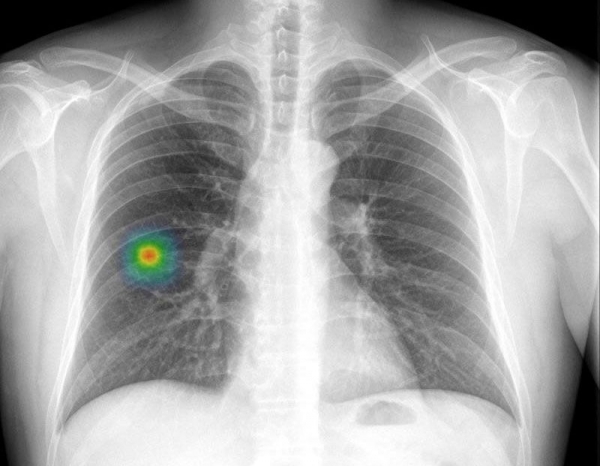

AI 판독 시스템은 해당 환자 폐 오른쪽 하부에서 이상징후를 포착했고 CT 등 추가 정밀검사 결과 폐암으로 확진됐다는 것이 연구팀의 설명이다.

조 교수 연구팀은 AI가 환자 응급실 내원 직후 기도삽관 뒤 촬영한 영상에선 58%의 가능성으로 이상이 있고, 며칠 후 추가 촬영한 영상에선 97%의 가능성을 제시했다고 밝혔다.